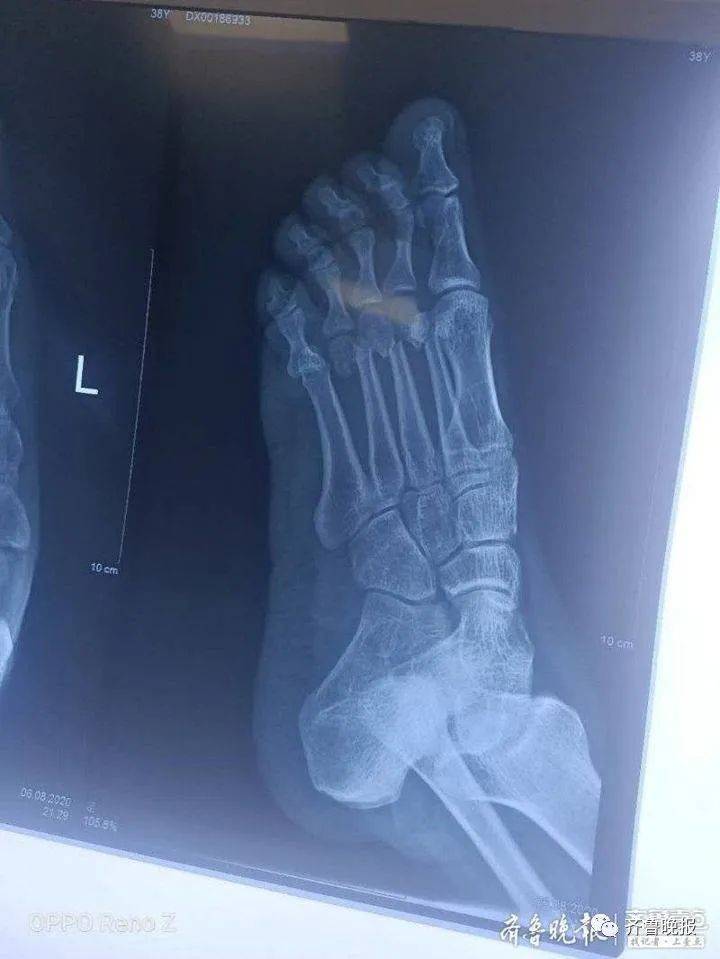

事后 , 采访人员从小区物业中心工作人员李保华口中得知 , 贺安友左脚受伤还是很严重的 , 中间三个脚趾骨折 , 小脚趾也出现错位的情况 。 “他当时光顾着救人了 , 没多大感觉 , 后来发现没法走路了 。 在医院检查后 , 院方立即给贺安友进行手术 , 用时两个半小时 , 手术成功 。 ”